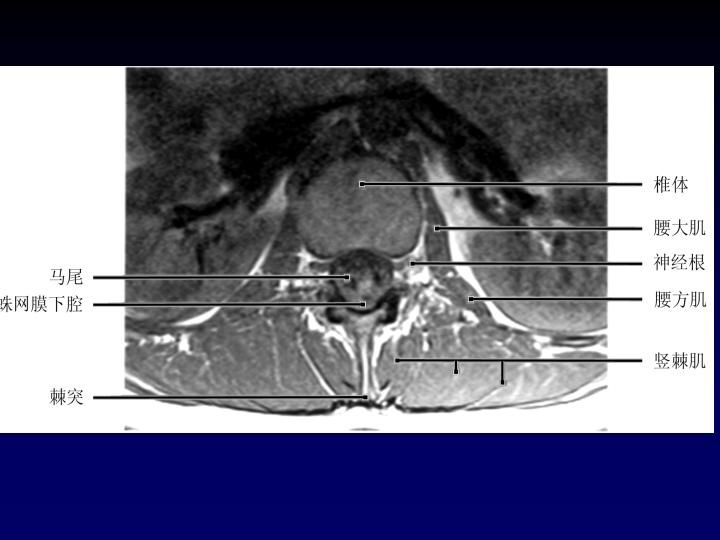

MRI

可提供腰椎管的矢状面、冠状面和轴位横断面上的影像。椎管狭窄以T2加权像显示较好,脑脊液为高信号,产生所谓“脊髓造影”的效果,而骨质增生,骨赘、间盘均为低信号,能清晰地显示椎管狭窄,以及对脊髓的压迫情况。但对肥大的黄韧带、骨质增生等的判断则不如较高清晰度CT扫描。

腰椎正常MRI解剖。

腰椎管狭窄MRI表现。